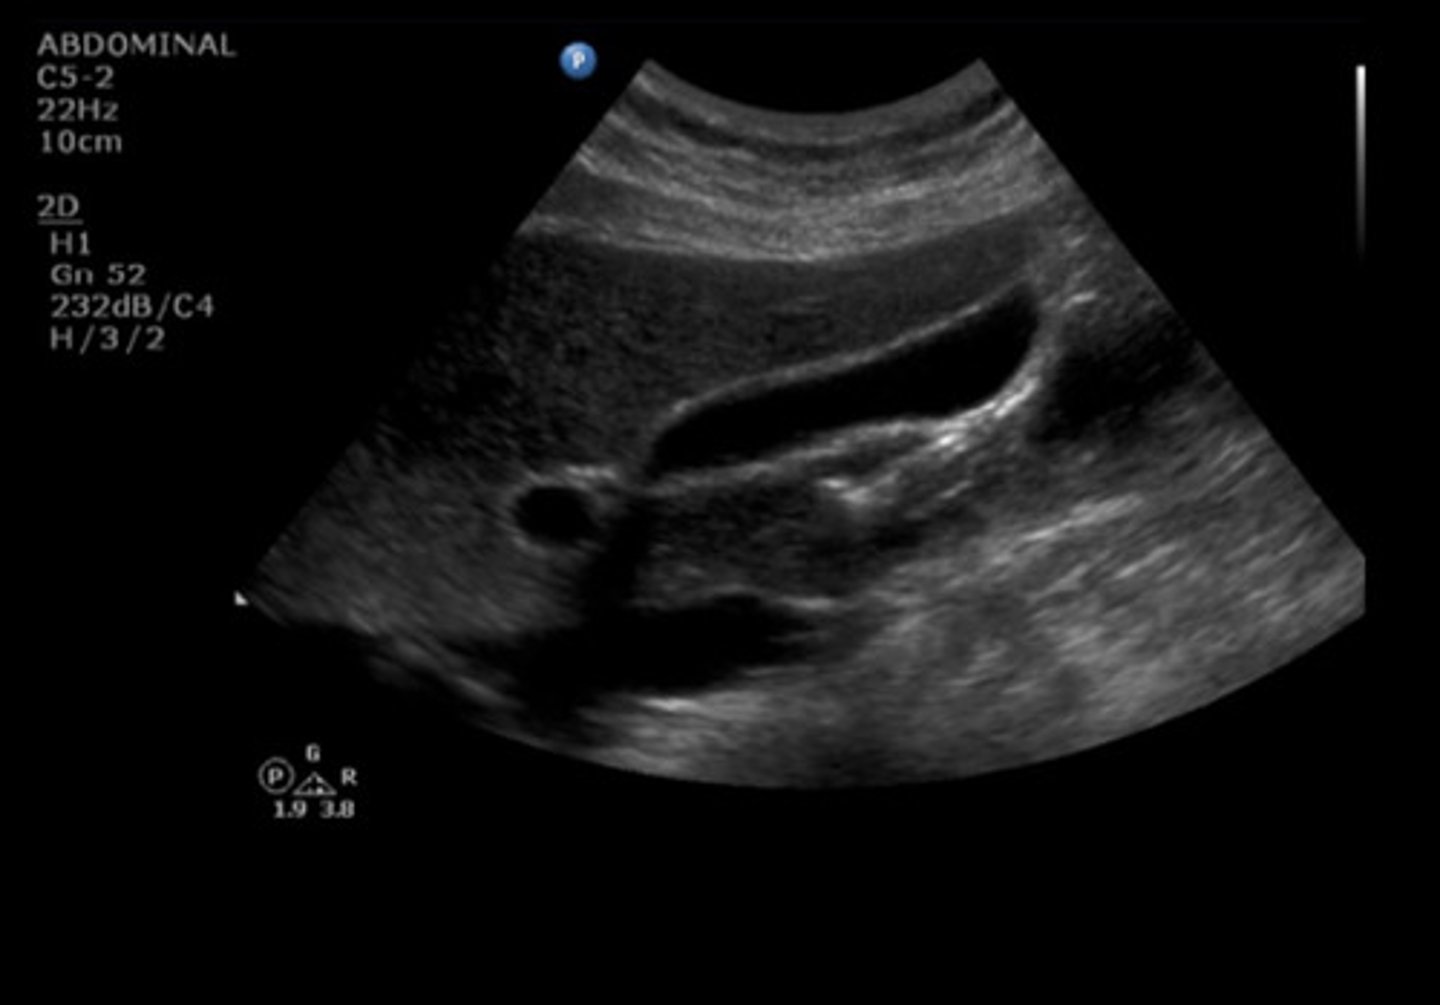

SAG GB MID SUPINE

Identify the following;